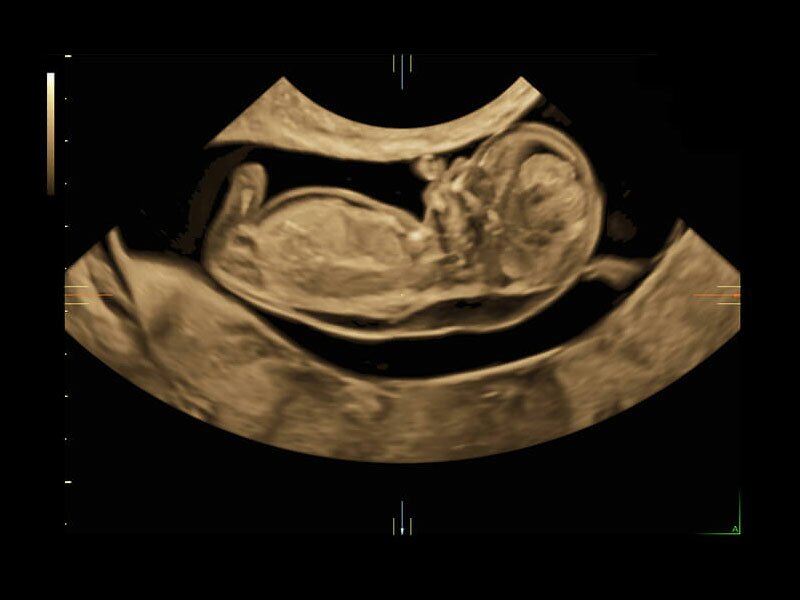

• Автоматическое определение плода в режиме 3D (SonoRenderLive) – позволяет значительно экономить время и получать изображение конечностей и лица плода в режимах 3D без артефактов и помех – система автоматически определяет границы конечностей и лица плода и выстраивает объемное изображение

Объемное сканирование Voluson — 3D/4D вашей мечты

Объемное УЗИ на Voluson E10 — это не просто потрясающе красивая картинка, это ценный инструмент получения дополнительной информации при обследовании женщин.

Voluson E10 поддерживает инновационные технологии формирования изображений — HDlive Silhouette и HDlive Flow, которые позволяют увидеть мельчайшие детали. Алгоритм SonoRenderlive упрощает рабочий процесс и дает возможность реконструировать изображение поверхностей, определяя область перехода между тканью и жидкостью.

• SonoRenderlive

• Улучшает объемную визуализацию за счет автоматического определения линии начала реконструкции при изображении поверхностей. При исследовании в режиме 4D функция SonoRenderlive непрерывно обновляет положение исходной линии с учетом движений плода.